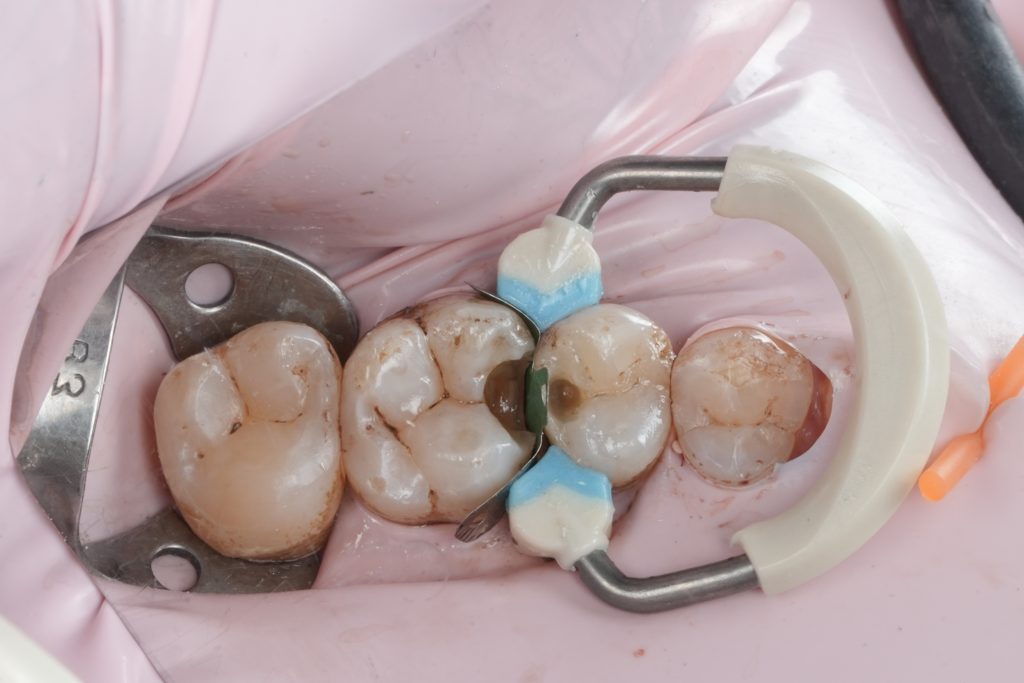

Matrix System and Proximal Control

A sectional matrix system with controlled separation was used to recreate natural proximal anatomy. Proper matrix adaptation allowed:

- Accurate emergence profile

- Tight, functional proximal contact

- Correct contour without overhangs

Wedges were placed to seal the gingival margin and provide slight tooth separation for predictable contact formation.